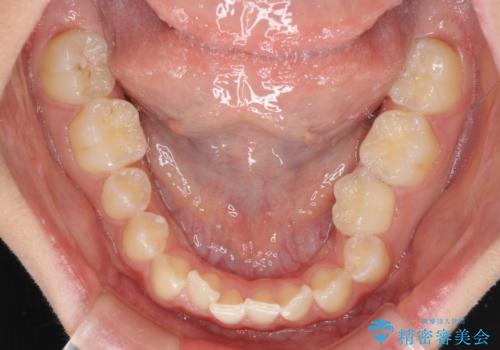

- 前歯の叢生と、奥歯の咬み合わせの悪さを気にして来院された患者様です。

左下には後続永久歯の欠損した乳歯が残存しており、叢生を相まって咬合関係が乱れていました。

乳歯は抜歯し、インビザラインにて矯正治療を行いながら、並行してインプラントによる補綴治療を行うこととしました。

矯正治療が終わるタイミングに合わせてインプラントの埋入を行っていたので、矯正治療を終了すると同時にセラミック補綴治療を行えました。

短期間でしっかりと治療を終えることができました。